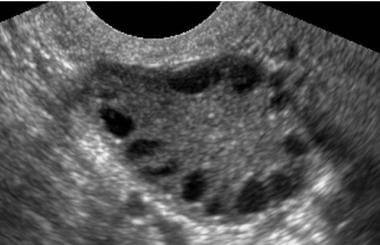

Características ultrassonográficas dos ovários policísticos

Os achados ultrassonográficos típicos de ovários policísticos incluem:

- Presença de folículos múltiplos: O critério mais importante é a presença de 12 ou mais folículos em cada ovário, com diâmetro variando entre 2 e 9 mm.

- Distribuição periférica dos folículos: Os folículos estão frequentemente dispostos na periferia do ovário, conferindo o aspecto clássico de “colar de pérolas” em cortes transversais.

- Aumento do volume ovariano: O volume do ovário é considerado aumentado se exceder 10 cm³. Em alguns casos, pode ser unilateral, mas em geral, a condição afeta ambos os ovários.

- Estroma ovariano: O aumento do estroma é um achado comum em mulheres com SOP, frequentemente correlacionado com a hiperprodução de androgênios.

Esses achados devem ser interpretados no contexto clínico e laboratorial, uma vez que a presença de ovários policísticos na ultrassonografia, isoladamente, não é suficiente para o diagnóstico de SOP.